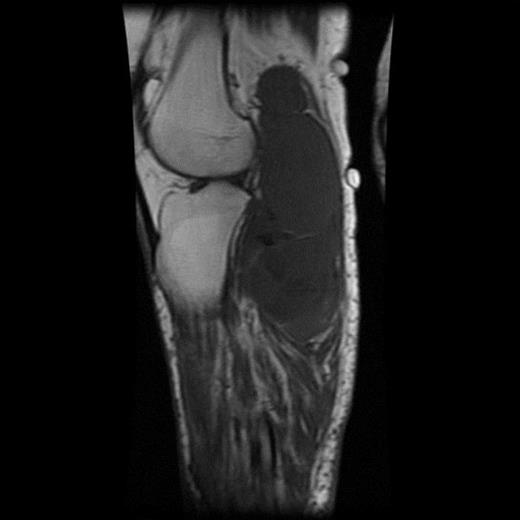

The MRI scan of the right knee (Figs 2 and 3) with gadolinium-enhancement showed a large mass lesion in the posterior aspect of the right knee extending into the popliteal fossa and into the upper third of the right leg having appearance of bursal pathology. Post gadolinium images showed evidence of circumferential rim enhancement but no internal enhancement indicating the presence of a fluid filled lesion. The mass (Figs 4 and 5) measured ∼8.39 × 6.14 × 12.72 cm and was seen between semimembranosus and biceps femoris muscles. There was no evidence of any infiltration of either the sciatic nerve or the popliteal vessels. A likely diagnosis of complicated synovial cyst with a differential diagnosis of haematoma was reported and a provisional diagnosis of Baker's cyst was established.

T1-weighted MRI image showing mass occupying whole of posterior aspect of knee extending to proximal portion of the leg.

Post gadolinium-enhanced MRI image showing circumferential lesion.